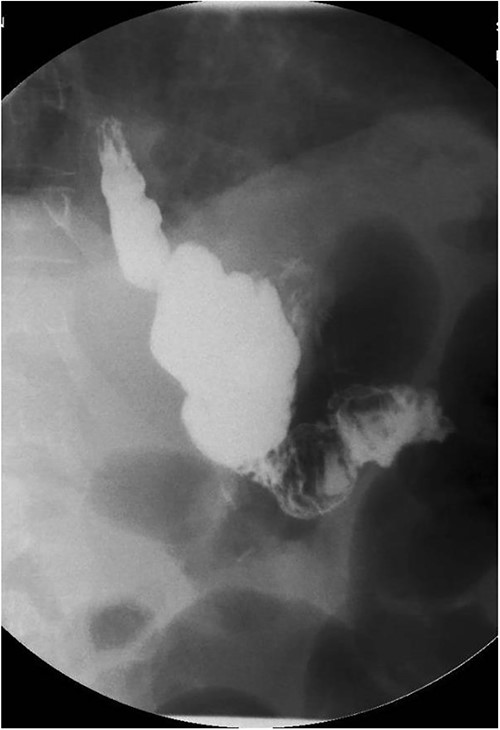

A 44-year-old-female with a surgical history notable for gastric bypass 12 years prior presented to the emergency department (ED) with a chief complaint of intermittent diarrhea, weight loss and nausea controlled by ondansetron. The patient had been admitted 8 months prior to presentation for abdominal pain and constipation that resolved with PO medications; however, she reported diarrhea since that time. The patient also reported that she was constantly hungry and eating high protein diet. She also complained of swelling of the bilateral arms, legs and abdomen for which her furosemide was increased on an outpatient basis. In the ED, her labs were significant for total protein = 4.2 gm/dl, albumin = 2.1 gm/dl, pre-albumin = 12.8 mg/dl, iron = 12 mcg/dl and calcium = 7.2 mg/dl. During the hospital course, the albumin was noted to decrease to 1.7 gm/dl. An abdominal ultrasound was performed and was only significant for a small amount of ascites. Gastroenterology was consulted and she was recommended with upper endoscopy, colonoscopy and a small bowel series in addition to total parenteral nutrition (TPN). Endoscopies were unremarkable and the small bowel series revealed a granular appearance of the jejunal mucosa with irregular thickening of the most proximal jejunal loop (Fig. 1). The patient was tolerating regular diet with persistent diarrhea; therefore, TPN was continued upon discharge to a rehabilitation facility in addition to her diet.

Small bowel series showing normal contrast transit from esophagus to stomach to small bowel loop.